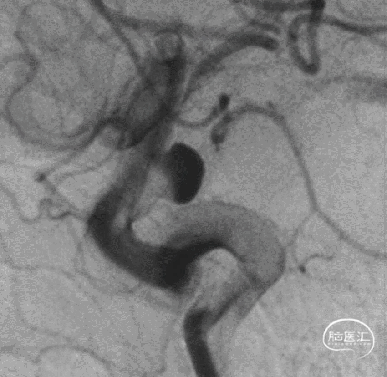

术后半年复查

5、FD植入后,动脉瘤明显造影剂瘀滞,效果显著。

6、Tubridge Plus材料改进后通体显影,可以更好观察支架的贴壁性及术中打开情况,提高释放安全性。

7、术后半年复查动脉瘤治愈,且未发生支架远近端狭窄及内膜过度增生,治疗效果满意。

8、同侧A1动脉瘤在FD保护下无变化。